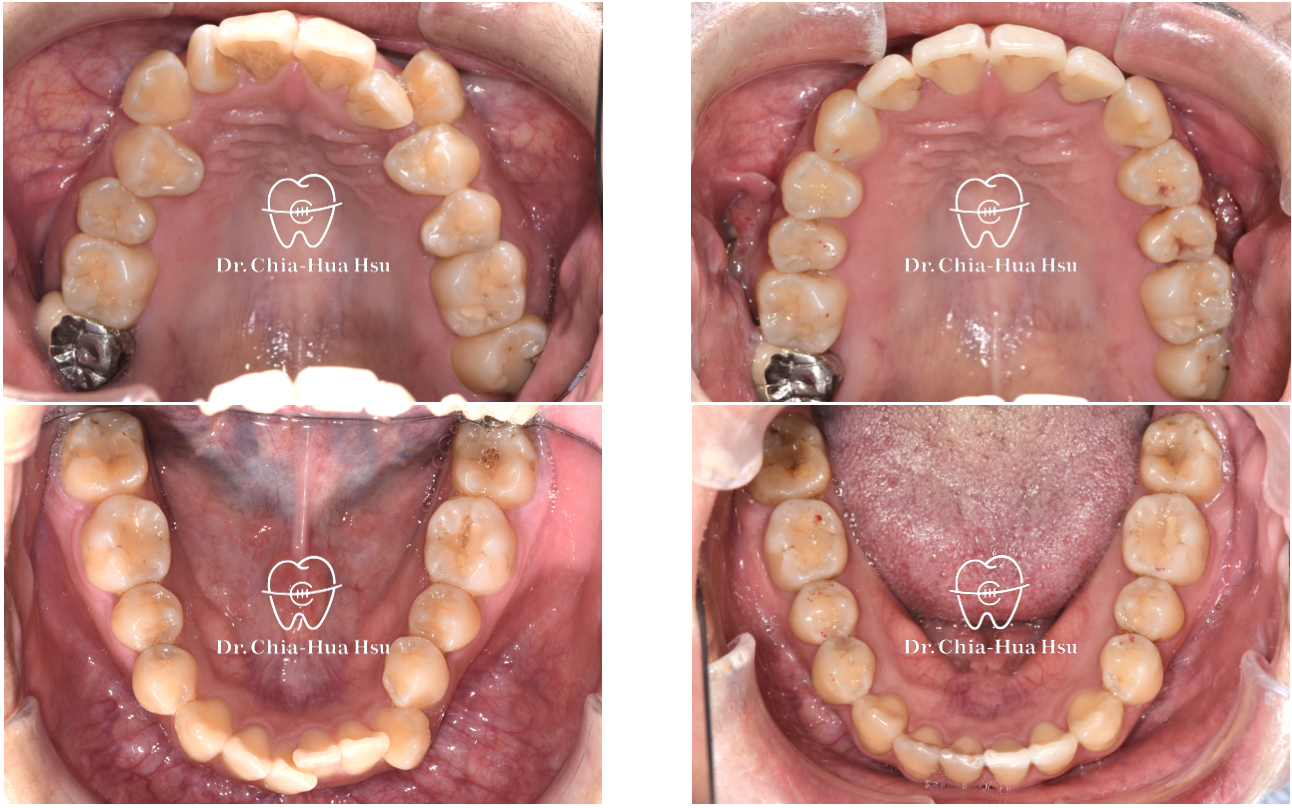

治療前

治療後

- 治療方式:雖然患者的齒列凌亂程度甚為嚴重,但是考量到患者外觀、門牙可以往外移動一些,而且尚有智齒空間可以退後,因此最後選擇隱適美治療,不拔小臼齒,利用骨釘與骨板退後齒列,同時讓門牙向外推出去一些,並撐寬牙弓以獲得空間。

- 治療時間:3 年。

患者治療中期搬到美國居住,每年只回診一次,不過因為患者有認真佩戴牙套,也定期拍照記錄讓許醫師遠端監控,才能順利完成治療! - 治療結果:齒列排齊,笑容更加燦爛與自信。